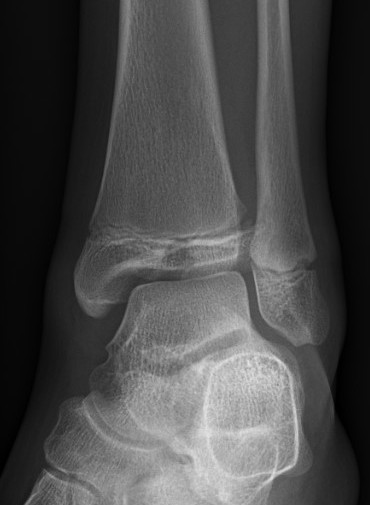

| SH I distal tibia / fibula | SH II distal tibia | SH III medial malleolus |

![]() |

| Low risk growth arrest | 40% risk growth arrest | 30% risk physeal bar |